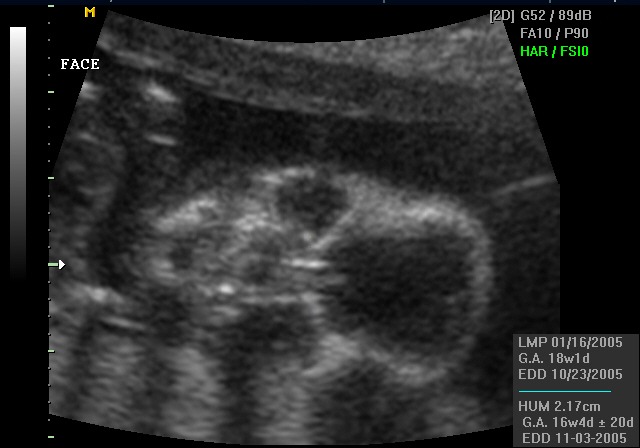

Yesterday we went into the Perinatologist to have a level two ultrasound performed. The tech was very nervous and was unsure about a few things. I was sure what was wrong after about ten minutes. When the tech left the room I mentioned it lightly to Bertha and we waited for the doctor to return.

He returned with the worst news I have ever heard in my life. Kennedy had multiple problems. A genetic defect. Spina bifida. A cyst on the brain. Clenched fists. Clubbed foot. The banana sign. A heart defect. They asked us to perform an amniocentesis, which we did.

The doctor thought Kennedy might be Trisomy 18. In a typical pregnancy, every cell in a baby's body has two copies of chromosome 18. In Trisomy 18, there are three. That one extra copy disrupts nearly everything — the heart, the lungs, the kidneys, the brain, the bones. It is also called Edwards syndrome. Most babies with T18 do not survive pregnancy. Of those who are born alive, most do not live beyond their first year. There is no treatment. There is no cure. There is only time, and how you choose to spend it.